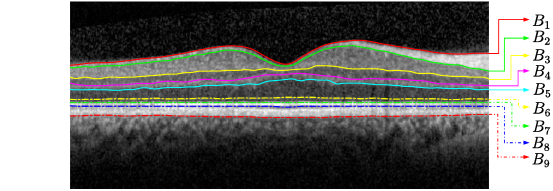

Data: 9 retinal layers boundaries were segmented for each image from in vivo OCT B-scans. 30 Spectralis SDOCT (ENVISU C class 2300, Bioptigen, axial resolution = 3.3μm𝜇𝑚\mu m, scan depth = 3.4mm𝑚𝑚mm, 32,000 A-scans per second) B-scans from 15 healthy adults were used for the work. The B-scan was imaged from the left and right eye of the healthy adults using a spectral domain OCT device with a chin rest to stabilise the head. The B-scan located at the foveal centre was identified from the lowest point in the foveal pit where the cone outer segments were elongated (indicating cone specialisation). The ground truth boundaries were manually generated by an experienced ophthalmologist. The dataset was randomly split into 20 training and 10 (5 are corrupted with high-level speckle noise using Matlab imnoise𝑖𝑚𝑛𝑜𝑖𝑠𝑒imnoise function with 0.8 variance) validation datasets. For image pre-processing, all images were cropped to extract only region of interest and were flattened using ground truth labels before training. The 9 retinal layer boundaries which can be segmented by the proposed method are shown in Fig 3.

Refer to caption

Figure 3: An example B-Scan OCT image centred at the macula, showing 9 target intra-retinal layer boundaries. The names of these boundaries labelled as notations B1subscript𝐵1B_{1},B2subscript𝐵2B_{2}B9subscript𝐵9B_{9} are summarised in Table 1.

Table 1: Notations for nine retinal boundaries, their corresponding names and abbreviations

Notation Name of retinal boundary/surface Abbreviation

B1subscript𝐵1B_{1} internal limiting membrane ILM

B2subscript𝐵2B_{2} outer boundary of the retinal nerve fibre layer RNFLo

B3subscript𝐵3B_{3} inner plexiform layer-inner nuclear layer IPL-INL

B4subscript𝐵4B_{4} inner nuclear layer-outer plexiform layer INL-OPL

B5subscript𝐵5B_{5} outer plexiform layer-outer nuclear layer OPL-ONL

B6subscript𝐵6B_{6} outer nuclear layer-inner segments of photoreceptors ONL-IS

B7subscript𝐵7B_{7} inner segments of photoreceptors-outer segments of photoreceptors IS-OS

B8subscript𝐵8B_{8} outer segments of of photoreceptors-retinal pigment epithelium OS-RPE

B9subscript𝐵9B_{9} retinal pigment epithelium-choroid RPE-CH